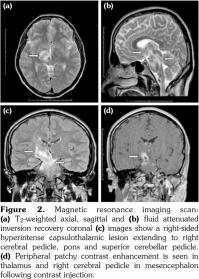

A contrast-enhanced cranial magnetic resonance imaging (MRI) was performed, which demonstrated a right-sided capsulothalamic lesion which was mild hypointense in T1-weighted images and hyperintense in T2-weighted/fluid attenuated inversion recovery images and extending from thalamus to the right cerebral pedicle, pons and superior cerebellar pedicle (Figure 2a-c). Peripheral patchy contrast enhancement was seen in thalamus and right cerebral pedicle in mesencephalon following contrast injection (Figure 2d). This lesion was interpreted as NB involvement of CNS. In diffusion MRI, defined lesion showed iso-hyperintense areas in diffusion-weighted images and low apparent diffusion coefficient. There were millimetric contrast-free parietal subcortical white matter lesions bilaterally in centrum semiovale and corona radiata level. Diffusion MRI findings were also interpreted as vasculitic lesions. Contrast- enhanced computed tomography (CT) and CT angiography of abdomen and thorax were performed for the exclusion of any thrombus or aneurysm and no abnormalities were observed.